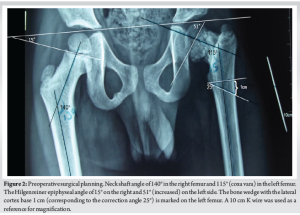

A 7-year-old boy presented with left hip pain for 1 year without any history of trauma or systemic illness. Antenatal and birth history were uneventful. Developmental history was normal. Movements of the left hip were restricted (especially internal rotation), with the left femur shortened by 2 cm. The Trendelenburg test was negative. Initial X-ray and computed tomography (CT) showed a left neck of femur transcervical fracture with a mixed area of lucency and sclerosis (predominant) in the femoral neck (Fig. 1).

Magnetic resonance imaging (MRI) showed signal intensity changes in the left femoral neck. NSA of the left femur was 115°, with Hilgenreiner epiphyseal (HE) angle of 51° (Fig. 2), and hence, surgical correction was required [1,2,3,4].